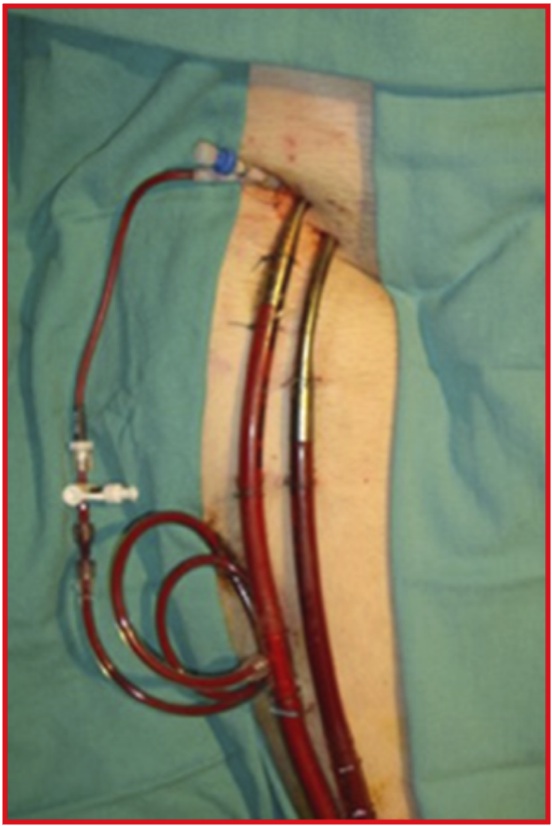

Stage I-get catheters into a femoral artery and femoral vein

Stage II-exchange these catheters for the enormous ECMO catheters vias guidewire and serial dilations

Stage III-attach them to the ECMO machine, which is run by specially trained ICU nurses for the first 45-60 minutes and then by a perfusionist.